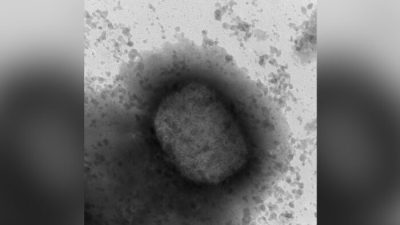

В Новом Южном Уэльсе зарегистрированы первые за 100 лет случаи потенциально смертельного респираторного заболевания. (Africa Studio/Shutterstock)